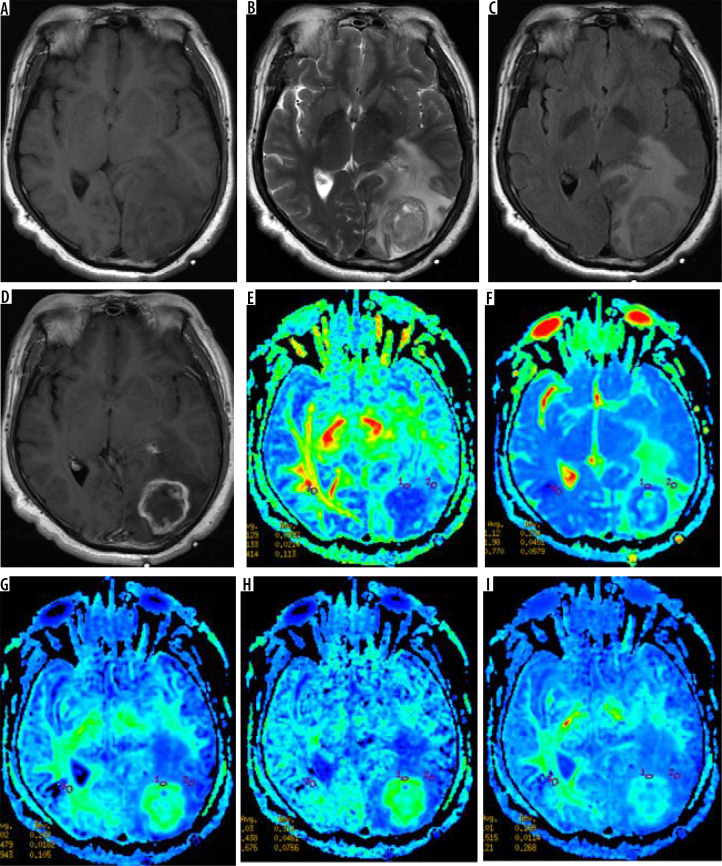

Material and methods: Twenty-five patients with WHO grade II gliomas were retrospectively included. Patients underwent routine MRI and DKI scanning before surgery, measuring tumoural solid portion, peritumoral oedema, and normal-appearing white matter (NAWM) DKI parameters, including fractional anisotropy (FA), mean diffusivity (MD), mean kurtosis (MK), axial kurtosis (Ka), and axial radial kurtosis (Kr). The DKI parameter corrections were made (tumour or oedema parameters values divided by the NAWM value) to obtain the rFA (ratio of FA), rMD (ratio of MD), rMK (ratio of MK), rKA (ratio of KA), and rKr (ratio of Kr) values. Postoperative specimens were made of wax blocks and analysed by Sanger gene sequencing. DKI parameters between the 2 groups were compared by independent sample t-tests. The ROC curve was used to analyse the diagnostic value of each parameter.

Results: Twenty-five patients were diagnosed with IDH-mutant (16 cases) and IDH-wild type (9 cases). The rFA and rMK values in the parenchymal region of IDH wild-type tumour were higher than those of IDH mutant, while the rMD values were lower than those of IDH mutant, and the difference between them was statistically significant (p < 0.05). The values of DKI parameters of peritumoral oedema in the 2 groups were not statistically significant.

Abstract Image